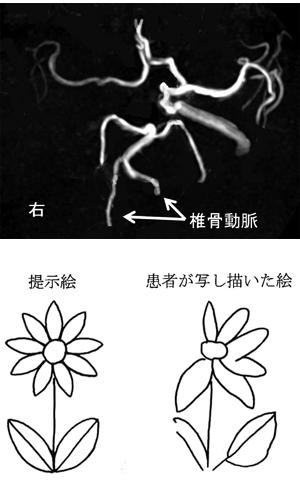

6

第35回 午前

|

作業療法士実地問題

47歳の右利きの女性。脳出血発症後2か月経過。ブルンストローム法ステージは上肢IV、手指IV、下肢V。麻痺側の感覚障害を認めた。図に発症時の出血部位(出血部位:網かけ)を示す。脳の他の部位には萎縮や低吸収域を認めなかった。患側上肢の分離運動を促通するための作業で適切でないのはどれか。

1

1

2

2

3

3

4

4

5

5